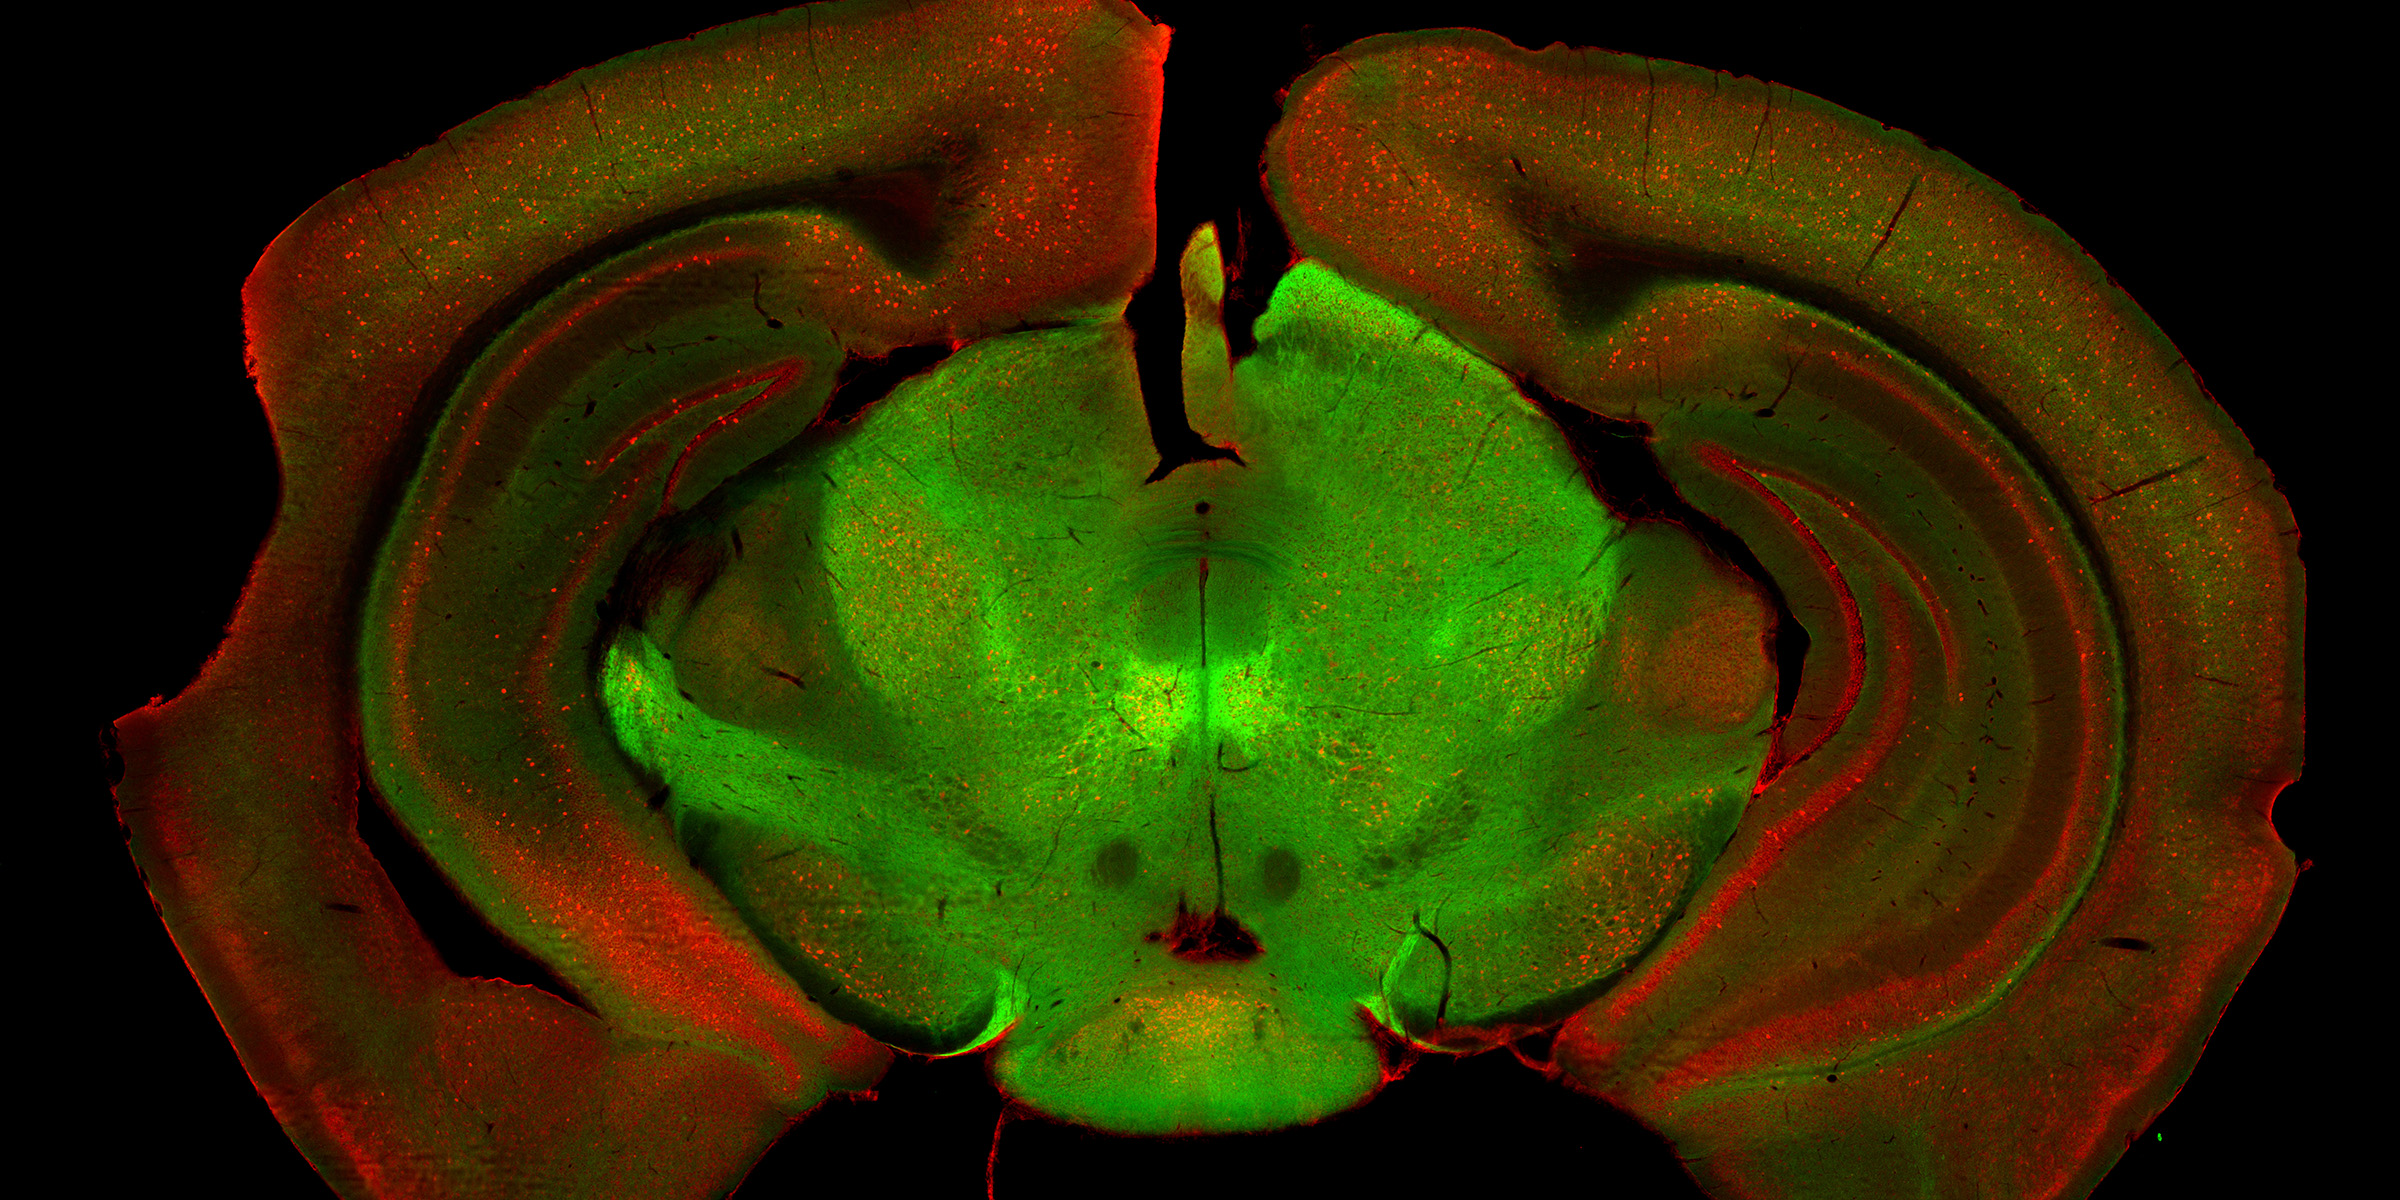

Egal ob wir unsere Arme, Beine oder den gesamten Körper bewegen, alles wird zentral von unserem Gehirn gesteuert. Dabei spielen verschiedene Hirnregionen und ihre Netzwerke eine wichtige Rolle. So auch die Substantia nigra, eine bislang wenig erforschte Gehirnregion. Wie eine Relaisstation empfängt und verteilt sie Signale, um eine gewünschte Bewegung zu koordinieren und auszuführen. Im Mausmodell hat die Forschungsgruppe von Prof. Kelly Tan am Biozentrum der Universität Basel nun zwei Zellpopulationen in dieser Hirnregion identifiziert, die für verschiedene Aspekte einer Bewegung verantwortlich sind.

Das Forschungsteam hat dazu die Substantia nigra anatomisch, genetisch und funktionell untersucht. Es zeigte sich, dass diese Region aus mehreren unterschiedlichen Typen von Nervenzellen besteht. Für zwei der Populationen haben die Forscher nun die genaue Funktion aufgeklärt: Während die eine Population für die Ingangsetzung einer gewünschten Bewegung verantwortlich ist, sorgt die zweite für deren Fortführung.